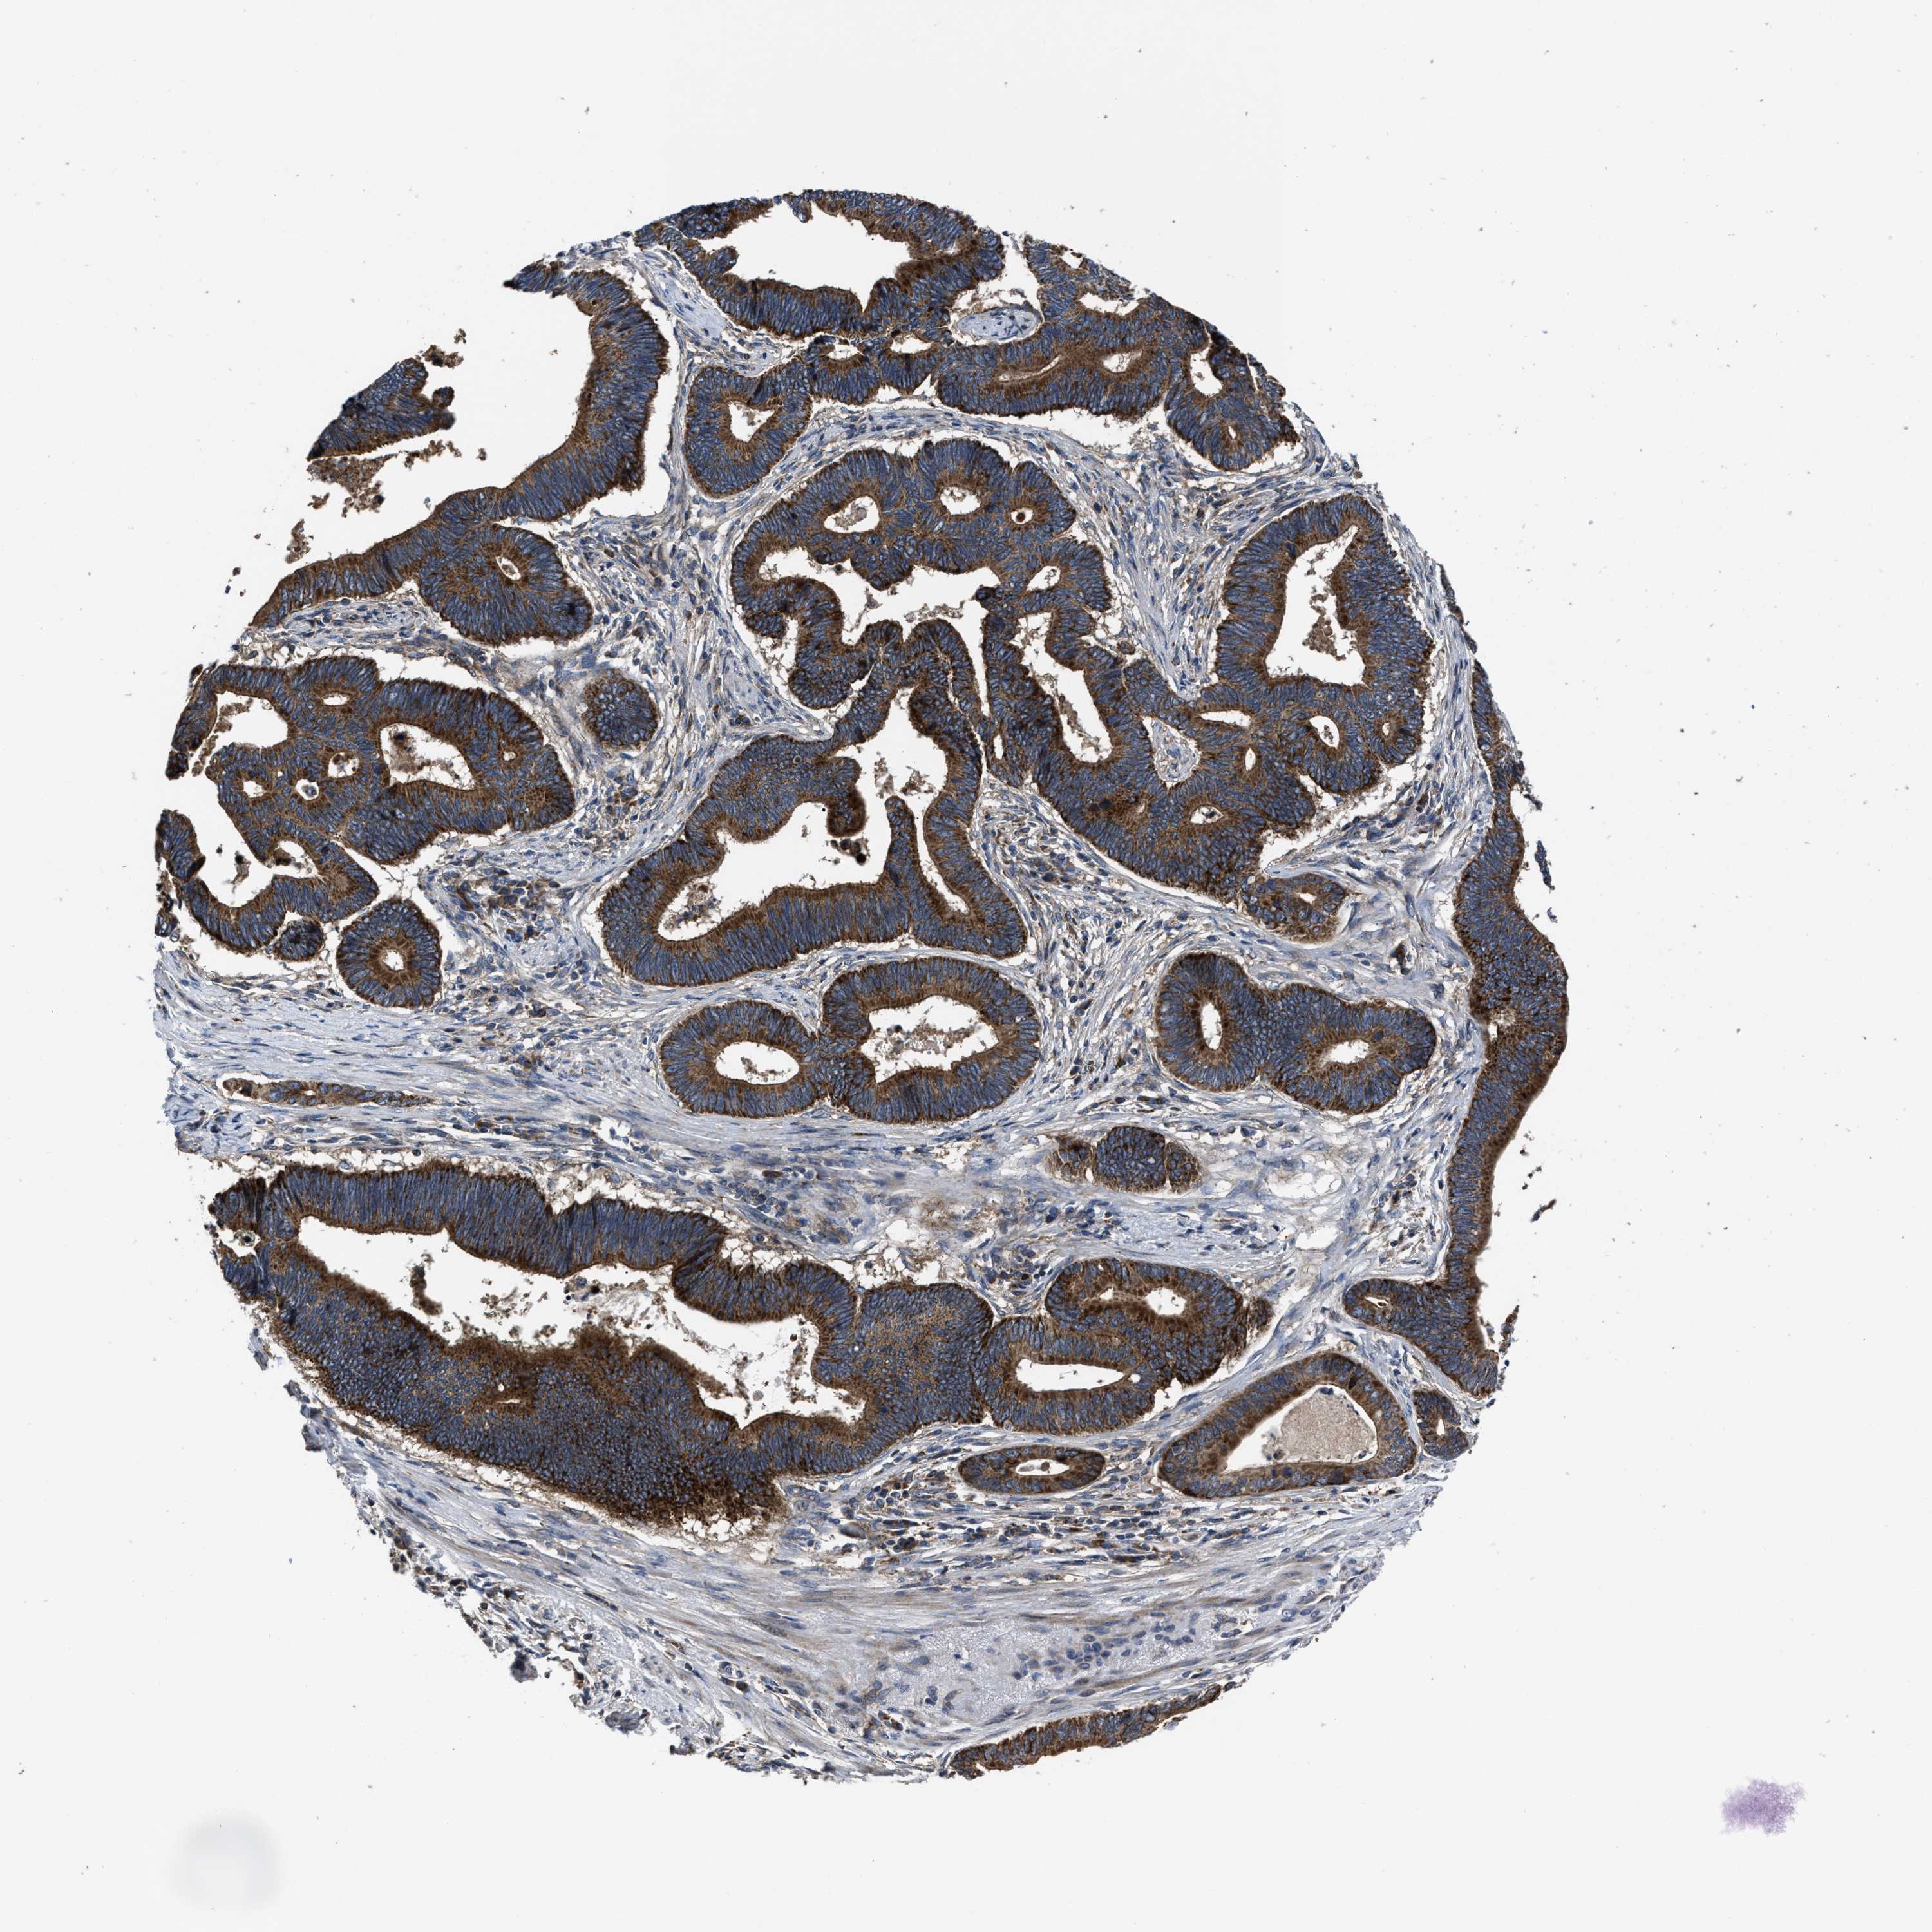

PANCREATIC CANCER - Protein expressioni

A mouse-over function shows sample information and annotation data. Click on an image to view it in a full screen mode. Samples can be filtered based on level of antibody staining by selecting one or several of the following categories: high, medium, low and not detected. The assay and annotation is described here.

Note that samples used for immunohistochemistry by the Human Protein Atlas do not correspond to samples in the TCGA dataset.

Antibody stainingi

Antibody staining in the annotated cell types in the current human tissue is reported as not detected, low, medium, or high, based on conventional immunohistochemistry profiling in selected tissues. This score is based on the combination of the staining intensity and fraction of stained cells.

Each image is clickable and will lead to virtual microscopy that enables deeper exploration of all samples and also displays staining intensity scores, fraction scores and subcellular localization as well as patient and tissue information for each sample.

Antibody HPA016450

Antibody HPA021079

Staining

High

Medium

Low

Not detected

Intensity

Strong

Moderate

Weak

Negative

Quantity

>75%

75%-25%

<25%

None

Location

Nuclear

Cytoplasmic/membranous

Cytoplasmic/membranous,nuclear

Adenocarcinoma, NOS